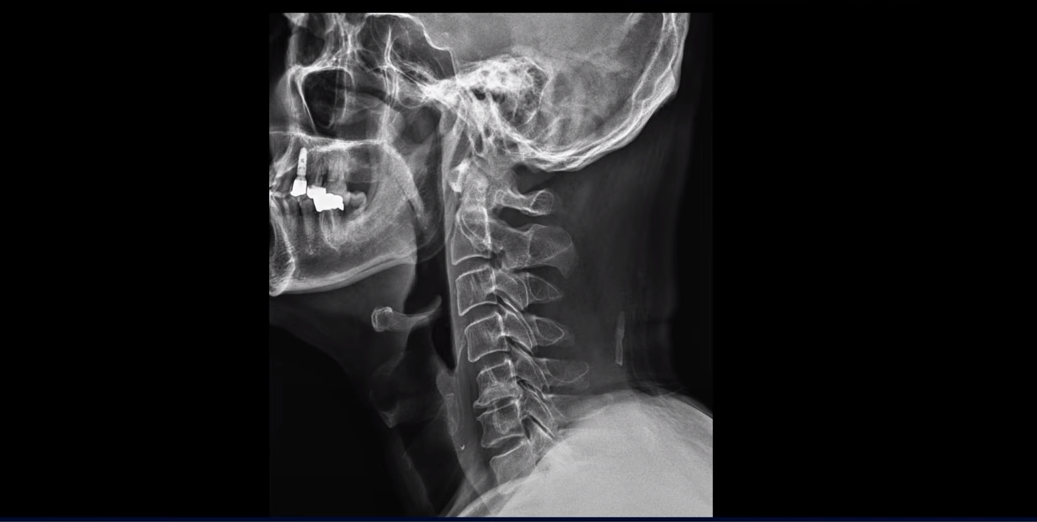

이분 목 x-ray를 보시면 일자목이고 이런 목 형태에서는 목 주변 근육이 만성적으로 뭉치고 굳어 있을 수밖에 없습니다.

이런 일자목, 거북목 형태의 목은, 특히 목 앞쪽의 근육들이 더 많이 뭉치고 단축되는데 그러면 목뼈들을 계속 잡아당기니까 신경 눌림이 더 심해질 수밖에 없습니다. 그러니까 이렇게 근육들이 뭉치고 굳어있고 단축된 상태에서는 잘 쉬면서 2주가 지나도 염증이 잘 가라앉지 않는 겁니다.